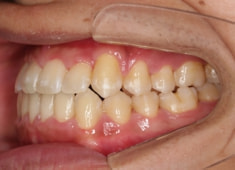

反対咬合+左上3番高位埋伏

(受け口+左上3番目の永久歯が上顎の中に埋まったままはえてきていない)

解説:残存している左上乳犬歯Cを抜歯し、そのスペースに左上3番を誘導しました。Cと犬歯ではスペースが足りないので、前歯をアドバンスさせ、反対咬合を同時に解消しております。

治療前

やはり統計通り、左上3番の埋伏です。

左上2番の歯根吸収が認められますが、保存不可能なレベルではありません。

成人の反対咬合なので、少し顎関節にダメージはありますが、重症ではありません。